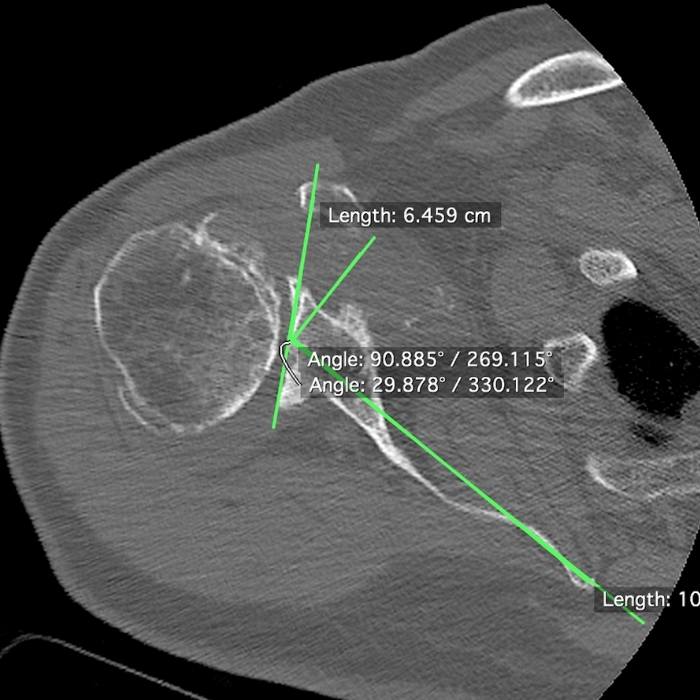

Rozpoznanie choroby zwyrodnieniowej barku wymaga dokładnego badania klinicznego polegającego na ocenie zakres ruchu i funkcji poszczególnych mięśni. Dodatkowo konieczne jest wykonanie badań obrazowych, najczęściej klasycznego badania RTG barku. Aby uzyskać dokładniejsze informacje, należy wykonać badanie MRI barku lub badanie tomografii komputerowej (CT). Badanie CT barku pozwala na dokładnie pomiary deformacji kostnych głowy kości ramiennej i panewki, co umożliwia techniczne planowanie operacji endoprotezy barku.